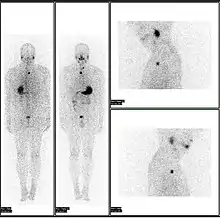

A nuclear medicine whole body bone scan. The nuclear medicine whole body bone scan is generally used in evaluations of various bone-related pathology, such as for bone pain, stress fracture, nonmalignant bone lesions, bone infections, or the spread of cancer to the bone.

A nuclear medicine SPECT liver scan with technetium-99m labeled autologous red blood cells. A focus of high uptake (arrow) in the liver is consistent with a hemangioma.